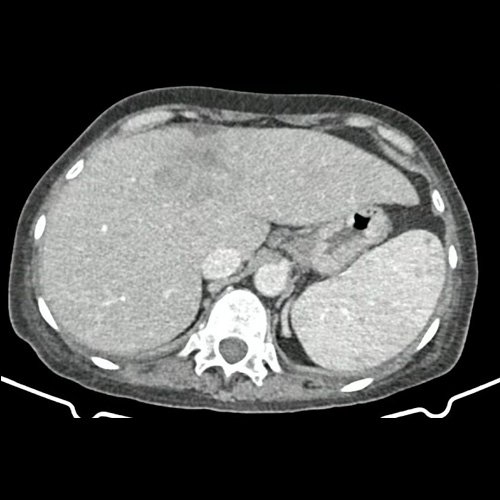

• TAC abdomen con contraste (un mes atrás): Múltiples estructuras ganglionares retroperitoneales, pre y lateroórticas, hiliares hepáticas y esplénicas aumentadas en número y de tamaño, de rango no megálico. El hígado es de forma, tamaño y situación habituales. Sus bordes son agudos. Se observa en segmento IV a –IVb, una lesión nodular hipodensa, ligeramente heterogénea, subcapsular, de bordes parcialmente definidos, con tendencia a homogeneizar con respecto al parénquima adyacente en fase de equilibrio. Mide 5,3 cm CC x 4 cm DT  x 3,7 cm AP. Hallazgos que podrían corresponder en primera instancia secundarismo hepático sin poder descartar otras etiologías. La vía biliar intra y extrahepática es de calibre conservado. La vesícula biliar es de forma, tamaño y situación normales, sin imágenes que sugieran la presencia de litiasis. Tener en cuenta que este método puede pasar por alto litiasis colesterínicas. Esplenomegalia homogénea. El eje esplenoportal es de calibre y trayecto conservado. El páncreas es de características normales. El conducto de Wirsung es de calibre conservado. Las glándulas adrenales son normales. Ambos riñones son de forma, tamaño y situación habituales. Sin evidencia de alteraciones calicopiélicas ni ureterales. La aorta, las arterias ilíacas primitivas, internas, externas y femorales, son de calibre y trayecto conservado. Trombos murales y calcificaciones parietales aortoiliacas. La vena cava inferior y las venas ilíacas primitivas, internas, externas y femorales son de calibre y trayecto conservados. Aisladas formaciones diverticulares en colon sigmoides, sin cambios inflamatorios al momento del examen. La vejiga escasamente replecionada, sonda balón en su interior. El útero es de forma, tamaño y situación conservada, en AVF, sin alteraciones densitométricas. No se observan alteraciones en topografía anexial. No se observa líquido libre ni neumoperitoneo Flebolitos pelvianos.

• TAC de abdomen y pelvis CC EV - informe preeliminar (Dia 30): En esta ocasión se observa hepatomegalia. Sus bordes son agudos. Continúa visualizándose de mayor tamaño, involucrando a casi la totalidad del segmento IV, una lesión nodular, de márgenes irregulares, hipodensa, ligeramente heterogénea, subcapsular, de bordes parcialmente definidos, Mide 9 cm CC x 6.5 cm DT x 5 cm AP (antes medía 5,3 cm CC x 4 cm DT x 3,7 cm AP). Actualmente se observa otra lesión nodular adyacente a la anterior descripta, en el segmento IVa/VIII, de similares características, que mide 3.5 cm DT x 3 cm AP, y otra en segmento IVa/II que mide 3 cm CC x 1.5 cm DT x 1 cm AP. Además se destacan otras dos lesiones, con similares características que las previas descriptas en segmento II que mide 19 mm DT x 15mm AP y en segmento VI que mide 14mm DT x 17mm AP. Hallazgos que podrían corresponder a secundarismo vs proceso infeccioso. Cotejar con datos clínicos de la paciente. Múltiples estructuras ganglionares retroperitoneales, pre y lateroórticas, hiliares hepáticas y esplénicas aumentadas en número y de tamaño, destacándose, en actual estudio,  una preaórtica derecha que mide 10 mm en su eje corto. En base pulmonar derecha se observan múltiples formaciones nodulares sólidas, irregulares, que realzan de manera heterogénea tras las administración de contraste E.V, como así también se observa otra de similares características en pulmón izquierdo en contacto con pericardio, la cual es la de mayor tamaño y mide 19 mm DT x 17mm AP. Hallazgos que obligan a descartar secundarismo pulmonar. Leve derrame pleural derecho. Hallazgos no visualizados en TC previa. Esplenomegalia que muestra densidad discretamente heterogénea, con algunas zonas de hiporrefuerzo de aspecto nodular. Trombos murales y calcificaciones parietales aortoiliacas. Aisladas formaciones diverticulares en colon sigmoides, sin cambios inflamatorios al momento del examen. Pequeña hernia inguinal epiploica izquierda, sin complicaciones agudas al momento del examen. Flebolitos pelvianos. Granuloma calcificado en TCS del glúteo izquierdo que mide 14mm. No se identifican alteraciones en las estructuras óseas visualizadas. Lesión osteoblásticas en cuerpo vertebral de L2.

TAC de abdomen y pelvis (internación previa)

TAC de abdomen y pelvis (Dia 30)